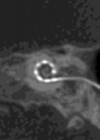

What’s new in implantable devices? New indications in cochlear implantation

For over 40 years, cochlear implant procedures have steadily increased. Outcomes for patients are improving as a result of modified surgical techniques, a wider portfolio of electrode arrays, advances in programming strategies, access to improved technology and a better understanding...